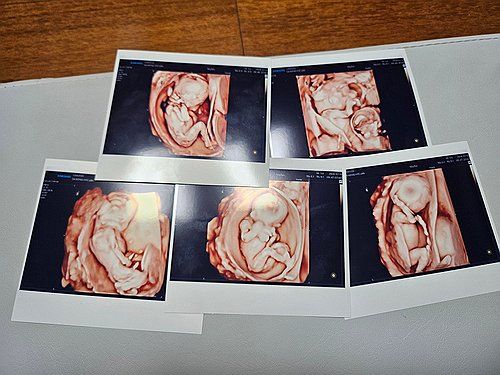

(서울=연합뉴스) 서울성모병원은 20일 낮 남자아이 3명과 여자아이 2명의 '오둥이'가 건강하게 태어났다고 밝혔다. 사진은 오둥이의 초음파 사진. 2024.9.20 [서울성모병원 제공. 재판매 및 DB 금지] photo@yna.co.kr

서울성모병원서 다섯쌍둥이 탄생 서울성모병원서 다섯쌍둥이 탄생